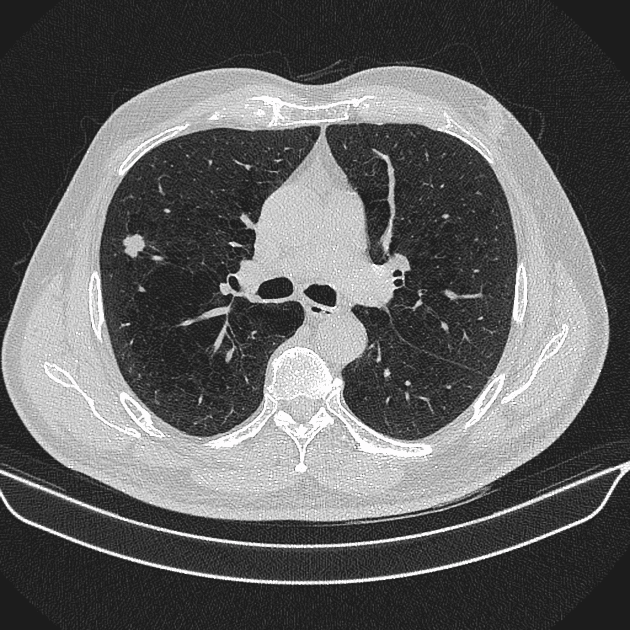

U phổi - Ảnh 4

U phổi

» Thông tin: Nam giới – 70 tuổi.

» Lâm sàng: Ho / Tiền sử hút thuốc lá.

# Ung thư biểu mô tuyến (Adenocarcinoma).